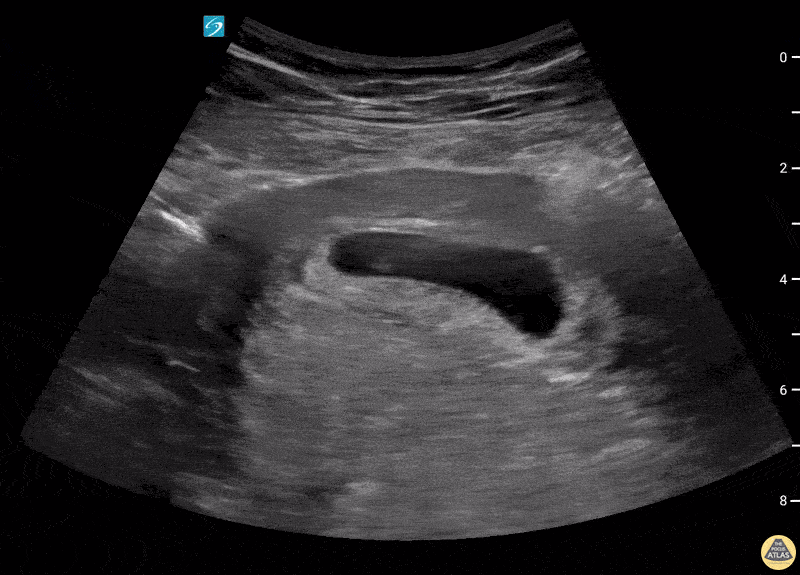

A 27-year-old female presented for evaluation of cough, congestion, decreased appetite, muscle aches, and fatigue. Patient was unsure of the date of her last menstrual period. This image is a transabdominal ultrasound of the uterus demonstrating a dichorionic diamniotic twin intrauterine pregnancy. The pregnancy was dated at approximately 8 weeks and 2 days, with fetal heart rates of 167 bpm and 174 bpm. Arthur Sieron BMBS, PGY-1 Emergency Medicine, Central Michigan University; Eric Spencer DO, PGY-3 Emergency Medicine, Central Michigan University; Halimah Hamidu, MS4 Central Michigan University College of Medicine.